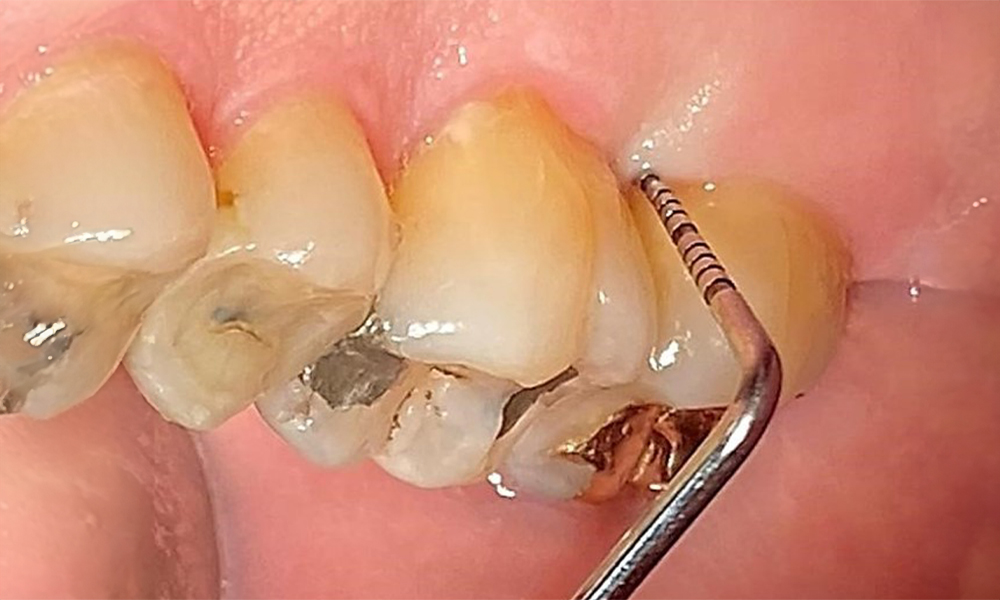

Okklusalansicht Oberkiefer. Insuffiziente Amalgamfüllung 14 mit Randspalt. © Dr. R. Krapf

Abb. 5 Okklusalansicht Oberkiefer. Insuffiziente Amalgamfüllung 14 mit Randspalt. © Dr. R. Krapf

Okklusalansicht Unterkiefer zur Darstellung der vorhandenen Restaurationen. © Dr. R. Krapf

Abb. 6 Okklusalansicht Unterkiefer zur Darstellung der vorhandenen Restaurationen. © Dr. R. Krapf

Der Patient hat ein vollbezahntes Gebiss mit 28 Zähnen, an welchen sich im Molaren- und Prämolarenbereich Amalgamfüllungen und Compositefüllungen befinden. An Zahn 14 zeigt sich ein sichtbarer klinischer Randspalt. Zahn 27 hat ein suffizientes Goldinlay. Zudem zeigen sich generalisierte Attritionen und Abrasionen. (Abb. 2, Abb. 3, Abb. 4, Abb. 5, Abb. 6)